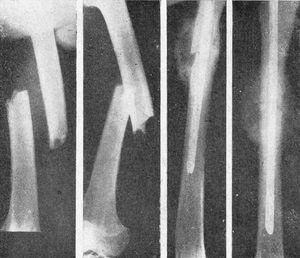

Figura 5. Fractura doble, antebrazo; enclavijamiento cerrado con alambres.

Figura 6. Fractura espiroidea tibia y conminuta peroné, que ni la extensión continua mantenía reducida. Enclavijamiento cerrado de la misma. La misma, consolidada.

Figura 7. Fractura de clavícula con gran desviación, en la que el enclavijamiento a cielo abierto consigue inmejorables resultados.

Figura 8. Fractura consolidada con desviación fragmentaria; osteotomía y enclavijamiento atípico; corrección de la desviación.